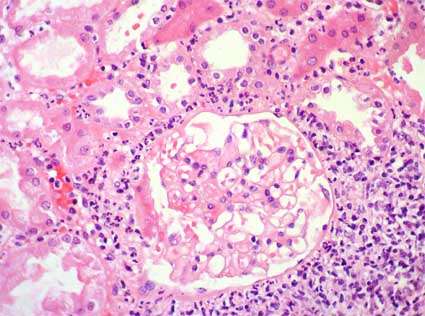

Un hallazgo notable en la biopsia renal de pacientes con nefropatía mesoamericana es la presencia de áreas de isquemia glomerular. Aunque no se considera un signo patognomónico, es altamente sugestivo de este síndrome, especialmente cuando se acompaña de lesiones tubulointersticiales crónicas. La isquemia glomerular puede ocurrir a pesar de que la enfermedad vascular subyacente sea leve, lo que sugiere que otros factores, posiblemente ambientales o relacionados con el estilo de vida, contribuyen al desarrollo del daño renal en estas áreas.